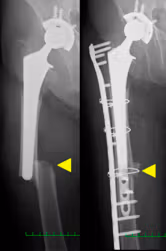

⑤人工股関節周囲骨折

人工股関節置換術後にその周囲の骨折が発生した場合、人工関節の存在から骨折部の固定が困難となります。また、骨折に伴い人工股関節のゆるみが発生した場合は、人工股関節再置換術が必要となります。